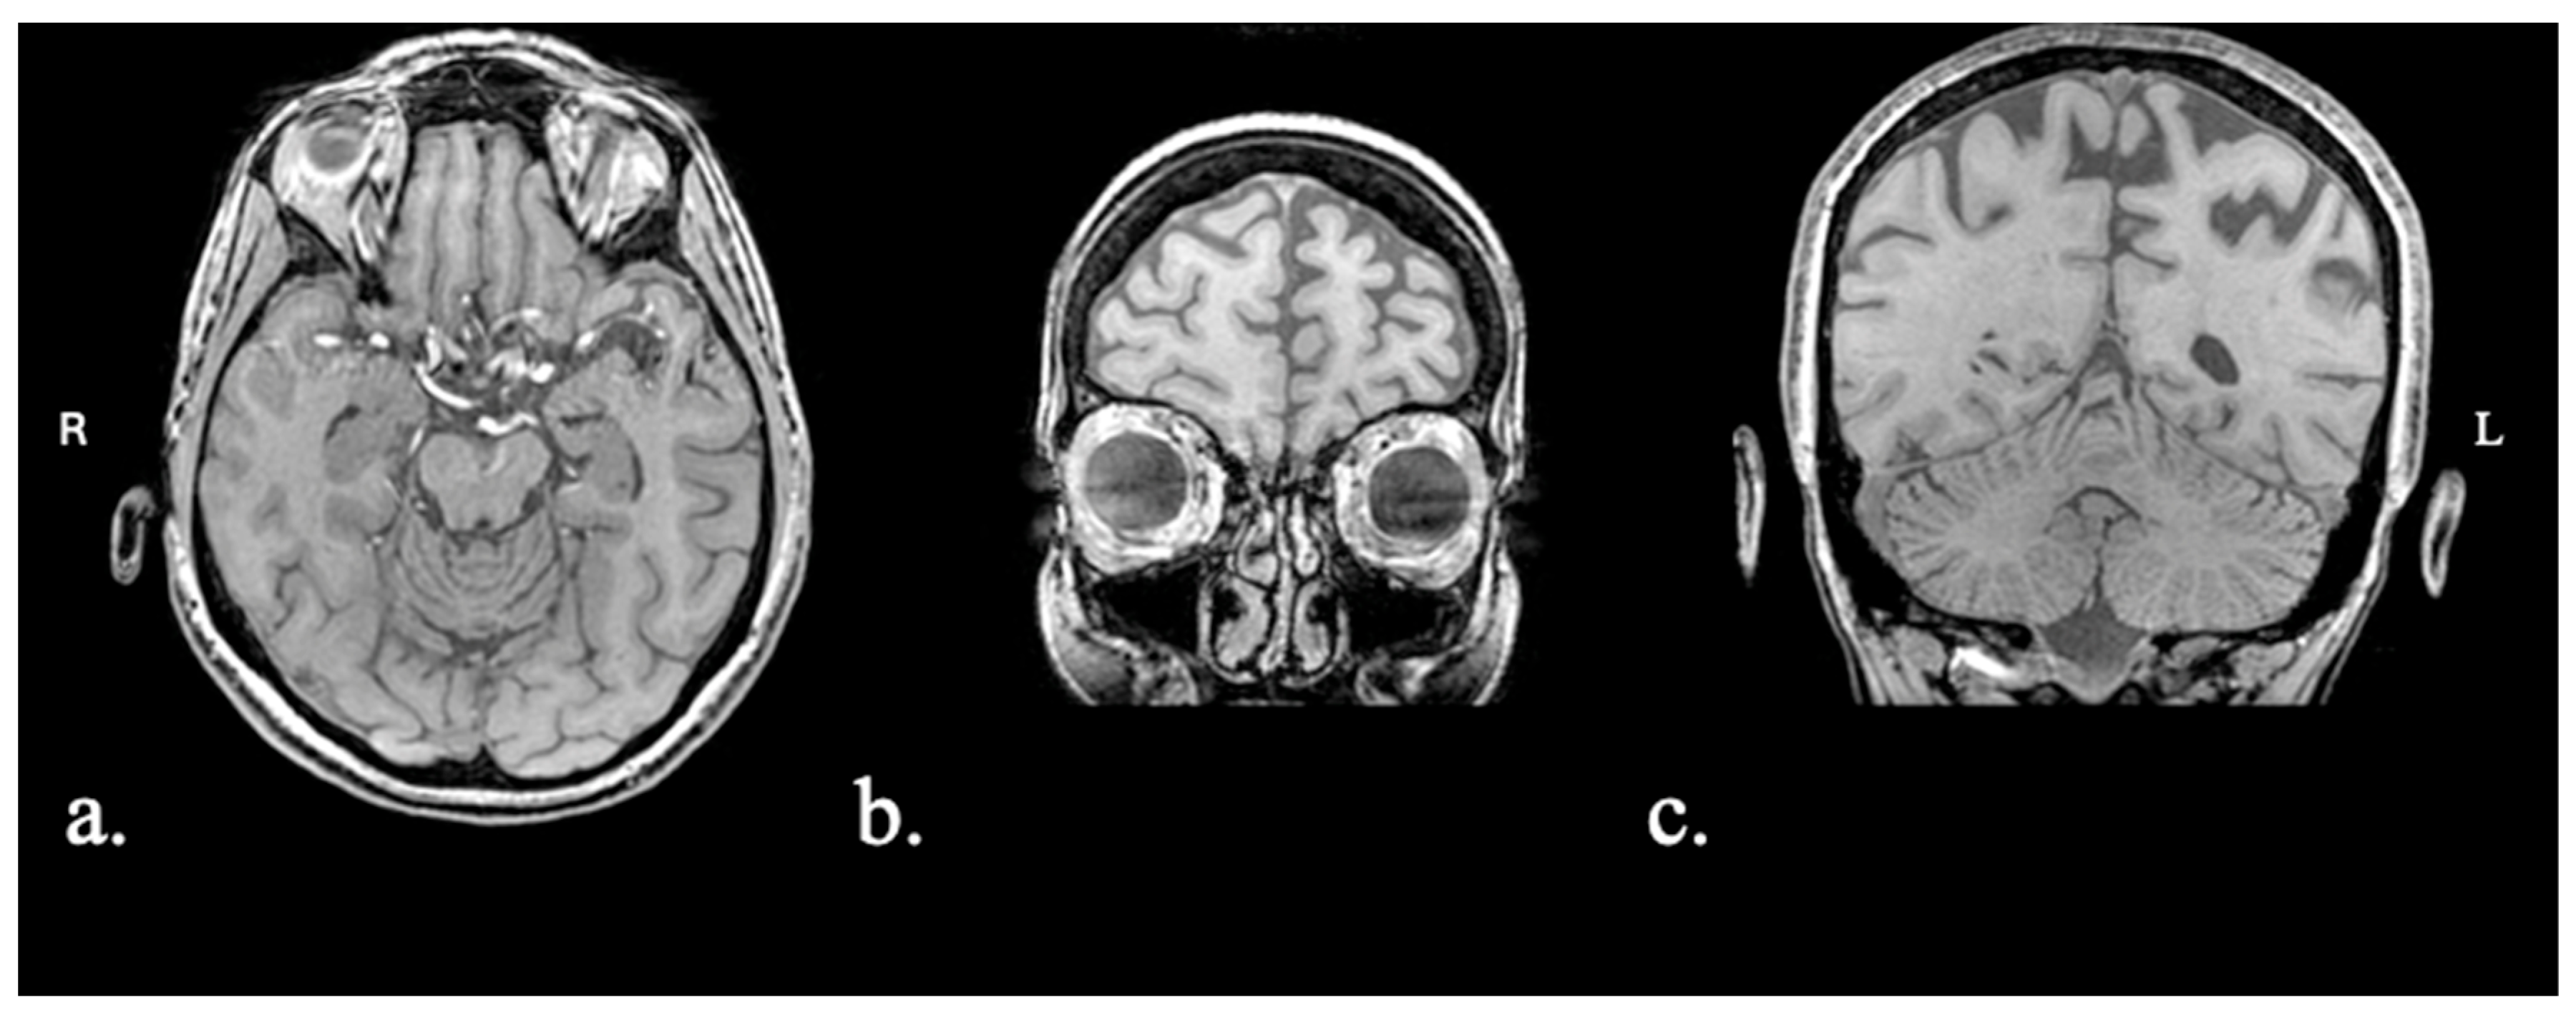

2.1.1. Patient FAY

2.1.2. Patient XTY

2.1.3. Patient ADY

2.1.4. Patient IZS